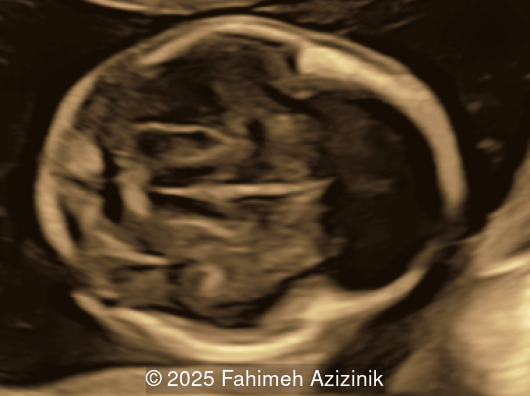

Image 2

• Bicoronal craniosynostosis

• Hypertelorism

• Frontal bossing

Bicoronal synostosis is the characteristic cranial hallmark of Apert syndrome, detectable sonographically from 18 weeks. Its most recognizable manifestation is turribrachycephaly, defined by an elevated cephalic index (typically >85–90%) and a tall cranial vault with marked frontal bossing [19]. On prenatal ultrasound, the face in Apert syndrome shows midface hypoplasia with a depressed nasal bridge, proptosis, hypertelorism, and frontal bossing. The extremities demonstrate syndactyly of both bone and soft tissue of the hands and feet with partial-to-complete fusion often involving second, third, and fourth digits, known as “mitten hands” and “socked feet”. In severe cases, all digits are fused, with the presence of a single nail known as “synonychia” [20]. Other ultrasound findings include mild ventriculomegaly, agenesis of the corpus callosum, deficient or absent septum pellucidum, and fusion of the cervical vertebrae at the level of C5-C6 [21]. Cardiovascular (atrial and ventricular septal defect) and genitourinary anomalies (hydronephrosis, and cryptorchidia) are present in 10% of patients [22]. Increased nuchal translucency in the first trimester [23], widely open metopic suture [24], and polyhydramnios [25] have also been reported. Three-dimensional (3D) ultrasound facilitates assessment of surface abnormalities of the face and extremities, and magnetic resonance imaging (MRI) can be used to evaluate associated intracranial conditions [26].